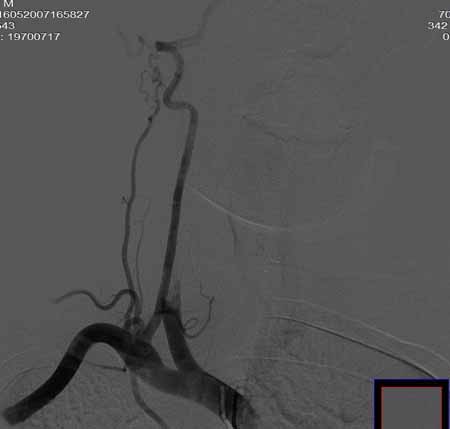

右侧颈总动脉闭塞(血栓形成),左侧大脑前动脉侧支、前交通动脉供应右侧大脑半球

右侧颈总动脉闭塞

右侧颈总动脉闭塞 ,左侧大脑前动脉侧支、前交通动脉供应右侧大脑半球,后交通部分开放 。缓慢代偿血流,分级3

右侧颈总动脉内见充盈缺损,提示血栓/栓子,原因:

1注意有无心房粘液瘤/血栓

2大动脉炎

抗凝治疗

右侧颈总a闭塞,右颈内颈外未显影,左侧未见异常,并通过wills环代偿右侧大脑半球血供